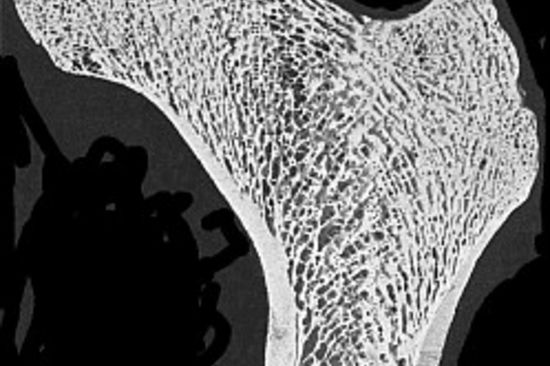

Abb.1: Querschnitt durch einen menschlichen Oberschenkelknochen

Oft liefert die Natur die besten Beispiele. Die Grundlagenforschungen am Institut für Leichtbau und Flugzeugbau zur Entwicklung neuer…